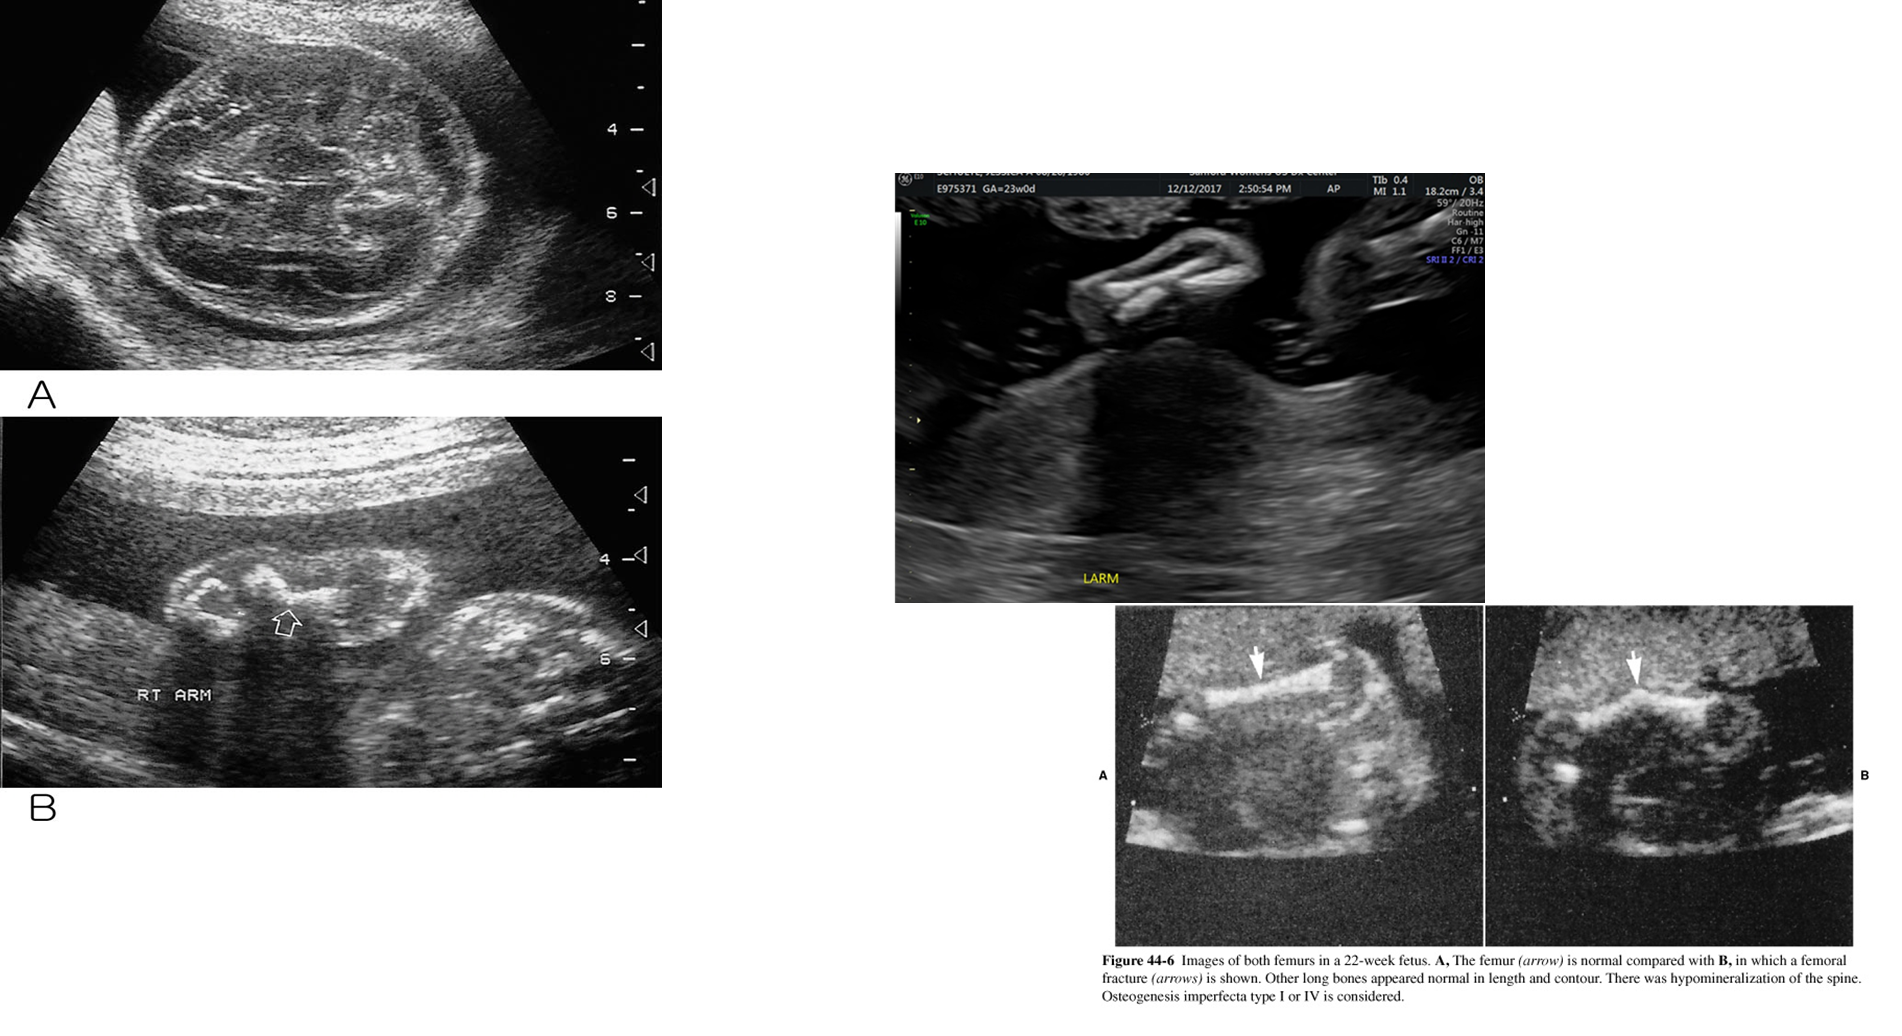

what is this image showing?

Osteogenesis Imperfecta

What are these images showing?